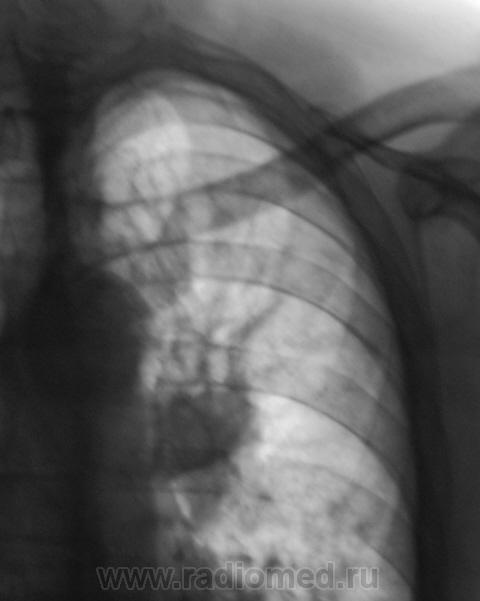

Центральный рак  с ателектазом  S3, на  снимке в прямой проекции то же присутствуют признаки уменьшения объема:  слева  диафрагма расположена выше обычного, средостение смещено влево, несмотря на поворот вправо при установке.

Вот, и позвонок, что-то не нравится...

Уплощены тела Th6-9, но, Валентин Львович, при таком кифозе я бы не стала оценивать позвонки по снимку легких даже цифровому, укладка другая требуется

Но, вот сидел сегодня, смотрел опять, ну кажутся они мне порозными.

Нет это не мтс, снижение высоты тел позвонков равномерное, с подчеркнутостью замыкательных пластин, измнения возрастного характера.

Да видимо действительно сенильный остеопороз. Хотя Th9 подозрительный..